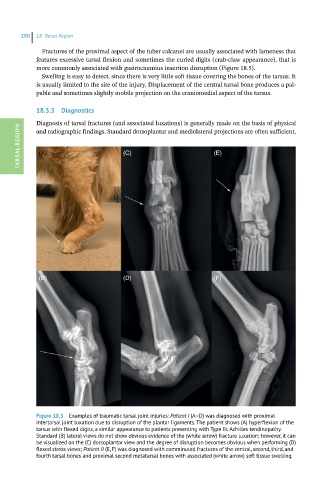

Figure 18.5 Examples of traumatic tarsal joint injuries: Patient I (A–D) was diagnosed with proximal

intertarsal joint luxation due to disruption of the plantar ligaments. The patient shows (A) hyperflexion of the

tarsus with flexed digits, a similar appearance to patients presenting with Type IIc Achilles tendinopathy.

Standard (B) lateral views do not show obvious evidence of the (white arrow) fracture luxation; however, it can

be visualized on the (C) dorsoplantar view and the degree of disruption becomes obvious when performing (D)

flexed stress views; Patient II (E, F) was diagnosed with comminuted fractures of the central, second, third, and

fourth tarsal bones and proximal second metatarsal bones with associated (white arrow) soft tissue swelling.